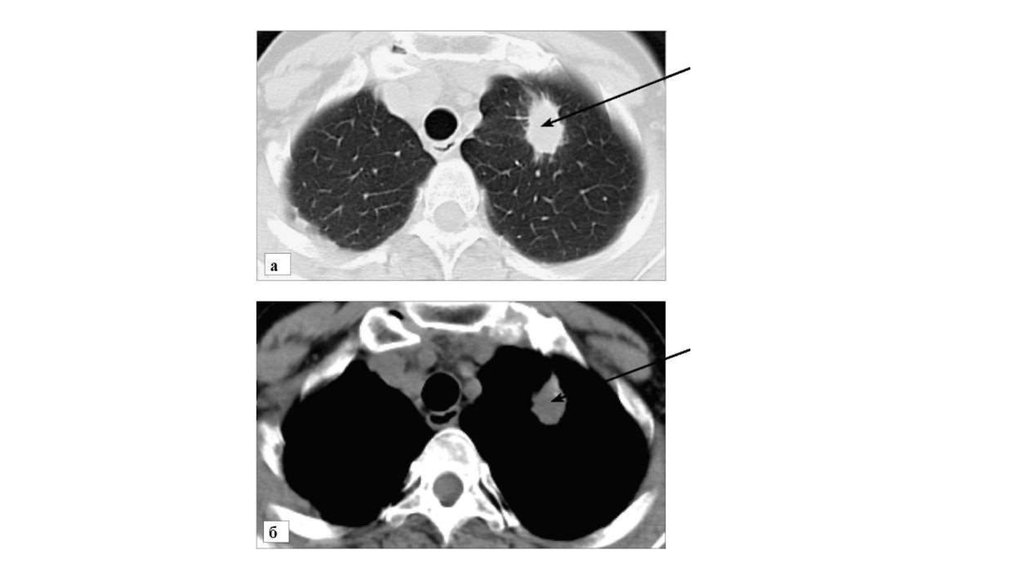

• Периферический рак верхней доли левого легкого. КТ. Стрелкой

указано мягкотканое образование верхней доли левого легкого, с

бугристыми, лучистыми контурами:

• а - томограмма в режиме «легочного» окна; б - томограмма в

режиме «мягкотканого» окна